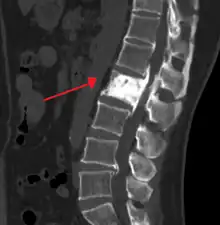

![]() | |

"This 92 year-old male patient presented for assessment of sudden inability to move half his body. An incidental finding was marked thickening of the calvarium. The diploic space is widened and there are ill-defined sclerotic and lucent areas throughout. The cortex is thickened and irregular. The findings probably correspond to the 'cotton wool spots' seen on plain films in the later stages of Paget’s disease." | |